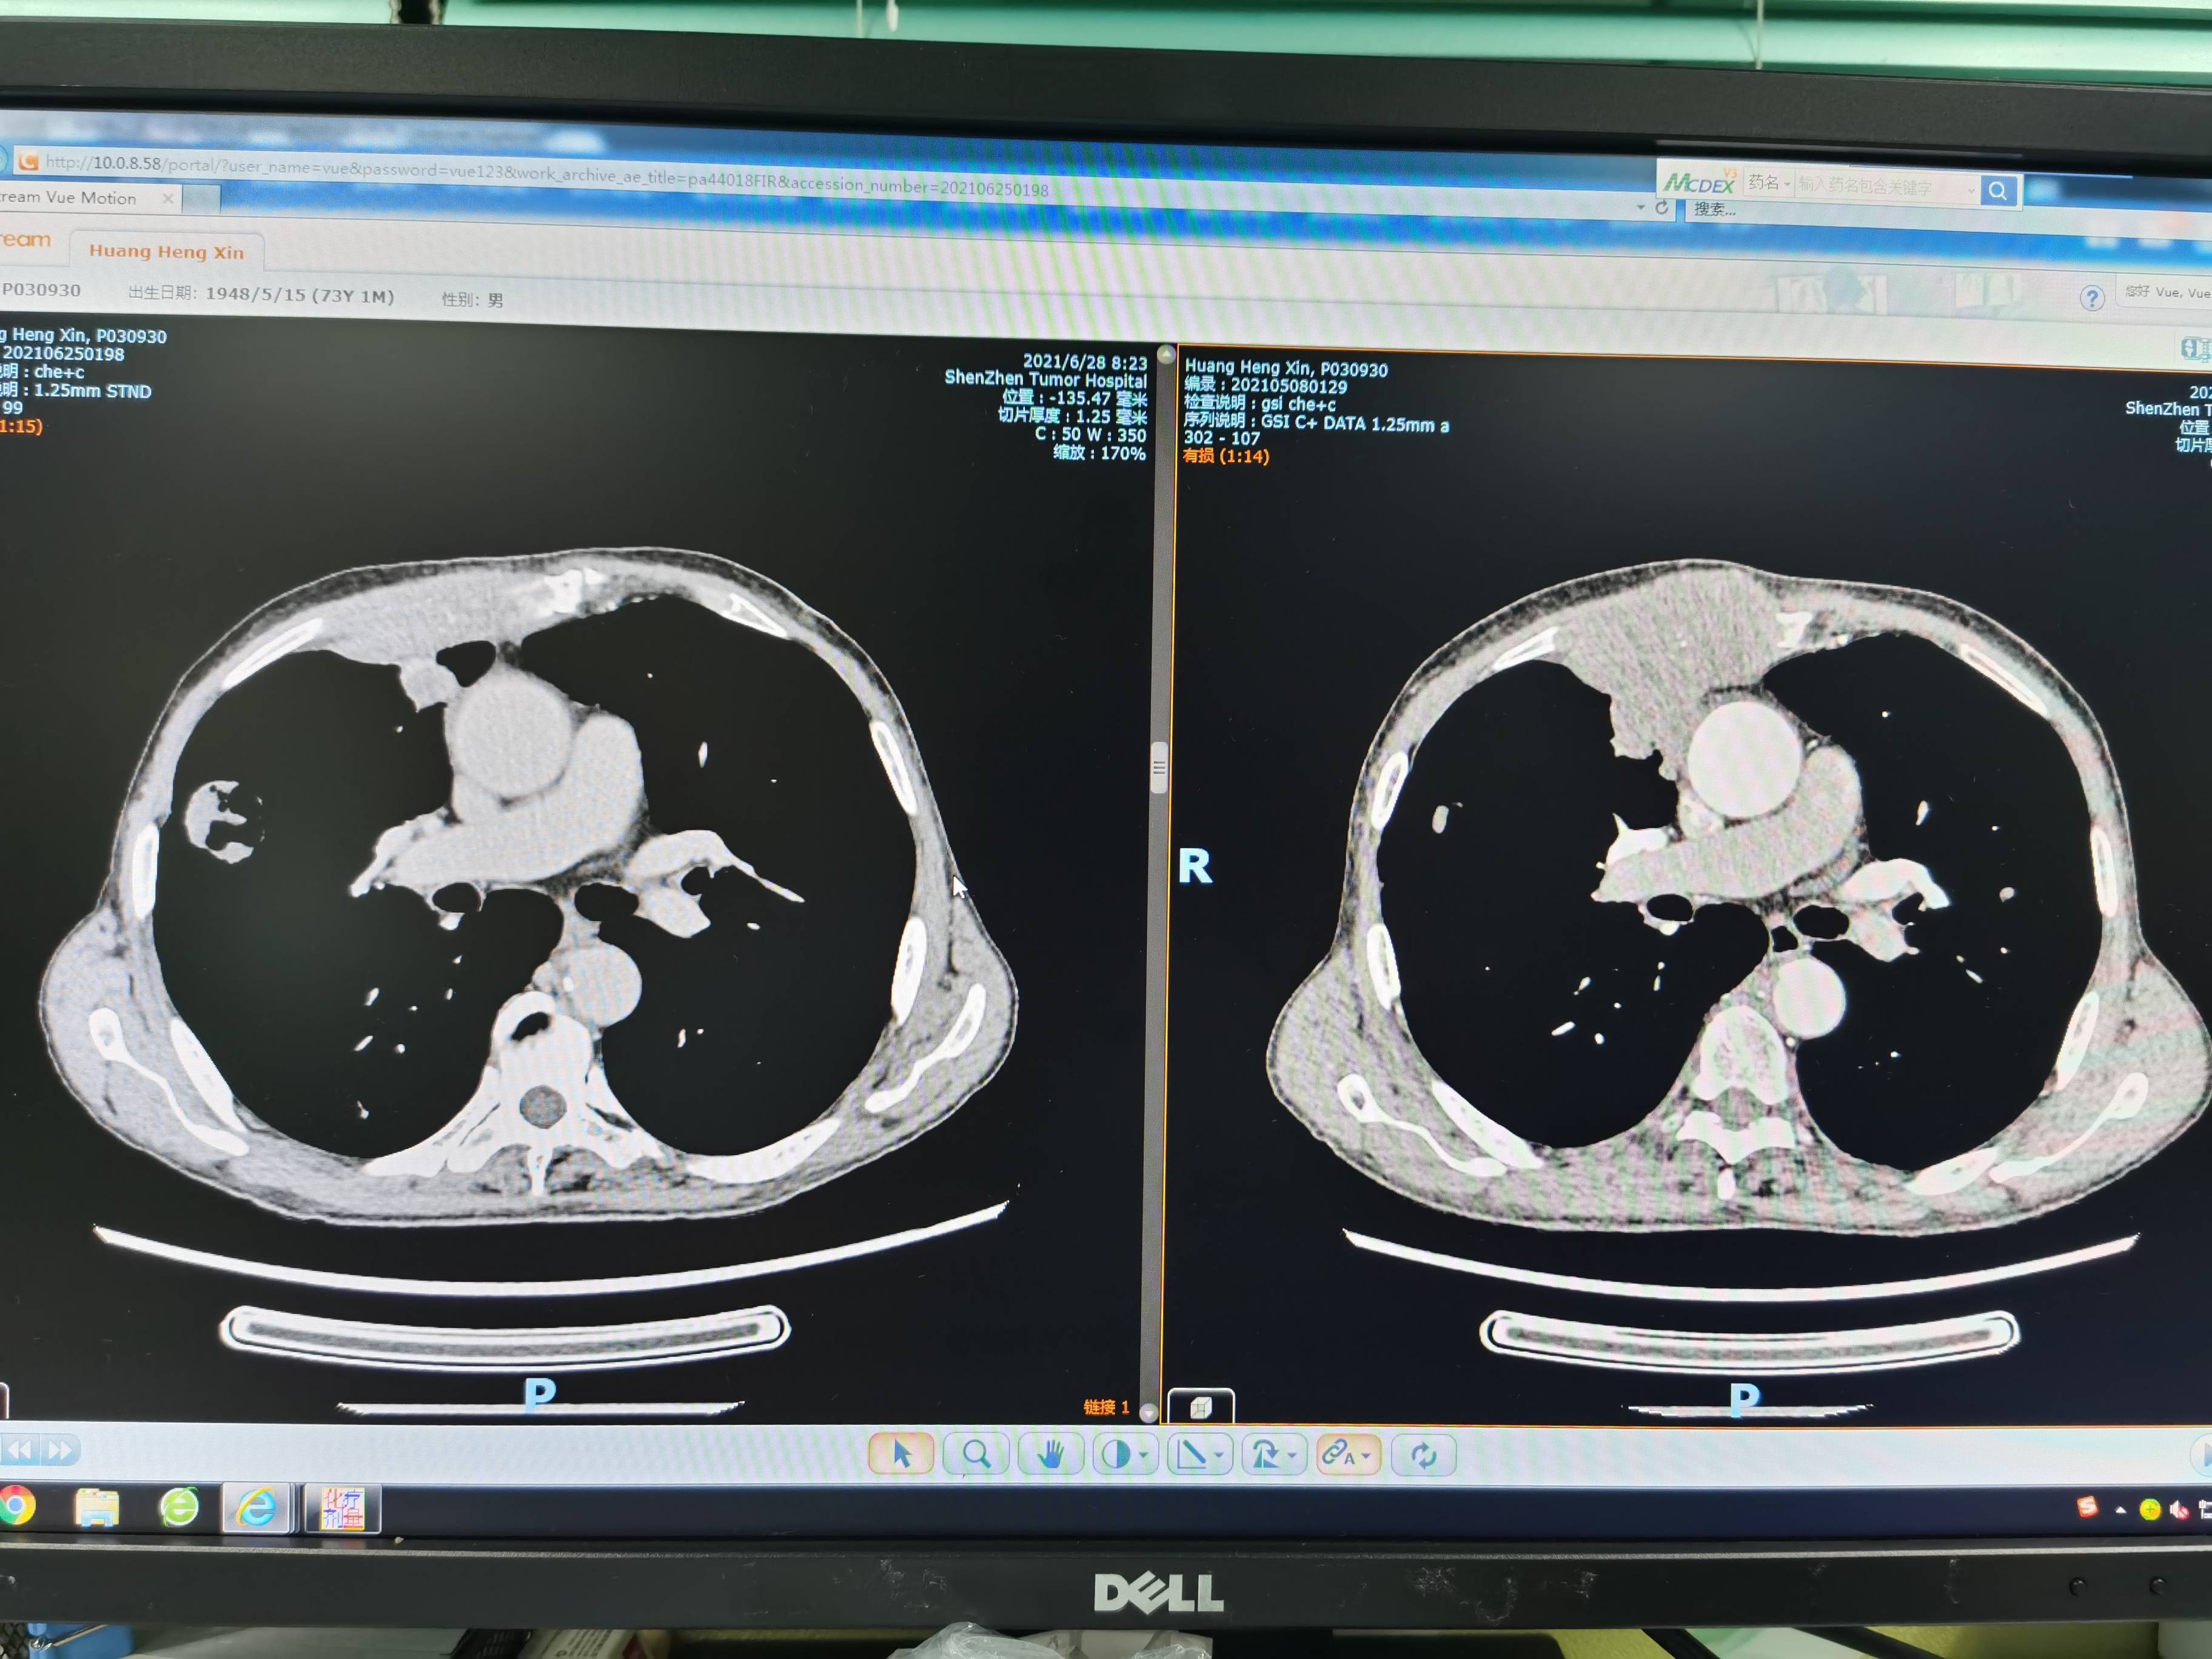

一般来说,二化周期后三化的时间点会有CT的复查,我们也不例外,也提醒主治医师别忘记安排。CT的结果还是不错的,有缩小,这也说明肿瘤发展暂时控制住了,其实不做CT我也能预想到这个结果,因为我爸的体感变好,肋骨疼痛也减轻或者没有,偶有白痰易咳出。不发烧,副作用方面就回家复查血常规,打两针低剂量升白针。三餐正常,所以本次CT算是预期内,而且本来前两化的效果大多数都比较理想的。

左边是治疗后,右边是治疗前